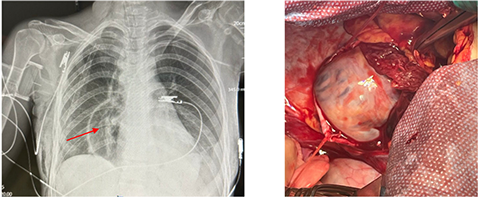

On POD 1, chest radiography revealed a pericardial effusion, necessitating pericardial drainage (Fig. 6a). Subsequently, the patient developed acute clinical deterioration due to hemopericardium, a complication of the drainage procedure, resulting in asystole. Cardiopulmonary resuscitation was performed, successfully restoring spontaneous circulation. The patient's condition rapidly declined, characterized by hypotension, cardiovascular and respiratory failure, and severe chest pain. Contrast-enhanced computed tomography following drainage revealed hydropericardium with imaging suggestive of Budd-Chiari syndrome.

A massive transfusion protocol was initiated. Emergency surgical intervention was performed, consisting of thoracotomy, pericardiotomy, hemostasis via suture ligation of the marginal coronary vein, pericardial fenestration, and drainage of the right pleural cavity (Fig. 6 b). On postoperative day (POD) 6, tracheostomy was performed due to prolonged mechanical ventilation. By POD 14, the patient demonstrated clinical signs of peritonitis with localized guarding in the right iliac fossa, prompting urgent diagnostic laparoscopy with abdominal and pelvic cavity drainage and sanitation. On POD 19, computed tomography revealed herniation of the colon into the left pleural cavity through the esophageal hiatus. Emergency re-laparoscopy was undertaken, including repositioning of the colon into the abdominal cavity, crurorrhaphy, and comprehensive sanitation with drainage. The patient’s condition gradually improved, with resolution of multiple organ dysfunction syndrome (MODS) and hepatic dysfunction. Bedside mobilization commenced, supported by comprehensive care in the intensive care unit (ICU), including mechanical ventilation, renal replacement therapy, intravenous fluid administration, and pharmacologic management. The patient was transferred from the ICU to the surgical ward on POD 26, began oral nutrition, and was discharged in stable condition with outpatient follow-up on POD 34.

Complications: multiple organ dysfunction syndrome (MODS) involving cardiovascular, respiratory, hepatic, and renal failure; post–cardiac arrest syndrome; hemopericardium; intrapericardial hematoma; superior and inferior vena cava syndrome; diaphragmatic herniation; colon translocation into the left pleural cavity; peritonitis; postoperative acute pancreatitis; acute kidney injury; ischemic hepatitis; internal jugular and subclavian vein thrombosis; post-pulmonary embolism syndrome; thoracic stomach syndrome (TSS); and bilateral hospital-acquired pneumonia.